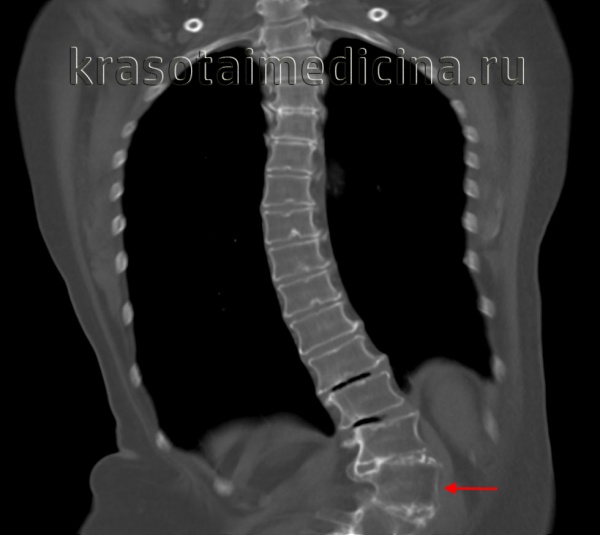

(Слева) КТ, фронтальный срез: признаки множественных аномалий сегментации позвоночника. Несколько правосторонних полу-позвонков не полностью сегментированы с соседними позвонками и формируют причудливую картину мальформации позвоночника с несколькими сколиотическими дугами искривления.

(Справа) 3D-реконструкция КТ этого же пациента с врожденным сколиозом на фоне множественных аномалий сегментации позвонков позволяет более полно охарактеризовать вклад каждой из имеющихся аномалий позвонков в деформацию и помогает выстроить наиболее оптимальный план лечения. (Слева) Фронтальная 3D-реконструкция: правосторонний L3 полупозвонок, являющийся причиной врожденной правосторонней сколиотической деформации. Слева на уровне этого полу позвонка видны рудиментарные корень дуги и задние элементы позвонка.